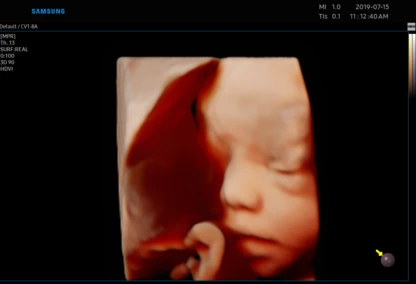

USG 3D dziecka w poradni ginekologicznej w Zambrowie –ocena NT, PAPP -A

Każdą kobietę w ciąży otaczamy kompleksową opieką, czuwając nad jej zdrowiem oraz prawidłowym rozwojem płodu. Podczas regularnych wizyt, zlecamy odpowiednie badania laboratoryjne. Korzystając z najnowszej generacji aparatu USG, przeprowadzamy bardzo dokładną diagnostykę obrazową – łącznie z USG 3D/4D płodu.

• Najnowsza generacja aparatu USG pozwala na przeprowadzanie dokładnej diagnostyki obrazowej, diagnostyki przepływów (Doppler).